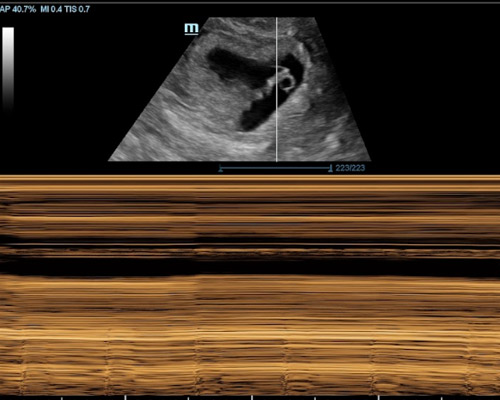

This scan uses ultrasound technology to observe important aspects such as heartbeat, movement, and overall activity. It allows the sonographer to assess how your baby is doing and provides a clear visual update.

For many families near Huddersfield, this experience is not just about medical reassurance. It also offers a chance to pause, reconnect, and enjoy seeing their baby moving on the screen again, which can be both comforting and memorable.

Our reassurance scan near Huddersfield is available from 13 -39 weeks. During this time, your baby’s movements and development are usually much easier to observe.